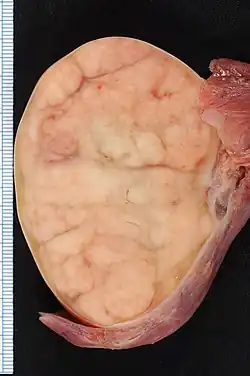

![]() | |

| 7.4 × 5.5-cm seminoma in a radical orchiectomy specimen. | |